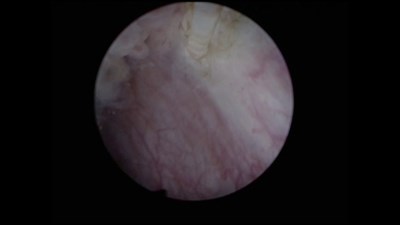

Сорокин Н.И. - «Диагностика и эндоскопическая визуализация опухоли мочевого пузыря»

Выступление на X Научно-практической конференции «Лопаткинские чтения» 16 февраля 2024 года.